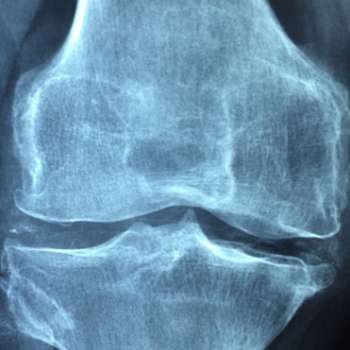

골다공증이 진행되면서 관절 주변의 뼈와 연골도 약해질 수 있습니다. 이는 관절 통증과 강직을 초래하며, 특히 아침에 일어날 때나 장시간 앉아 있다가 일어날 때 증상이 더 심해질 수 있습니다. 이러한 증상은 일상적인 움직임과 활동을 방해하고, 환자의 이동성을 제한합니다. 관절 통증은 특히 무릎, 엉덩이, 손목 등의 부위에서 흔히 발생하며, 이는 환자의 생활의 질을 저하시킬 수 있습니다.